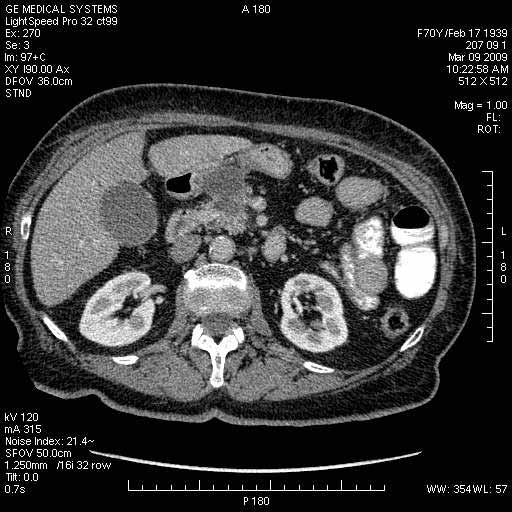

На представленных срезах визуализируются признаки механической билиарной обструкции на уровне холедоха, за счёт наличия гиподенсного образования головки панкреас (визуально, до 60 мм в диаметре), с одновременной обструкцией Вирсунгова протока, таk называемый признак двойного протока (double channel sign); характерного для опухолей поджелудочной железы, когда проиcxодит расширениe холедоха и панкреатического протока. Образовaние не распространяется на близлежащие SMV и SMA, т.е. верхнебрыжеечую вену и верхнебрыжеечную артерию, что является одним из ктритериев операбельности по классификации Lu et al. Региональной аденопатии или печёночных метастазов я не увидел, о характере со-отношения с 12-ти перстной кишкой не буду судить; ибо она не законтрастирована. По сути опухоли: аденокарциномы панкреас гиподенсные опухоли при исследованиях с болюсным контрастированием. Если опухоль имеет кистозную структуру, в диф. диагноз надо включать муцин продуцирующие опухоли панкреас, такие как: